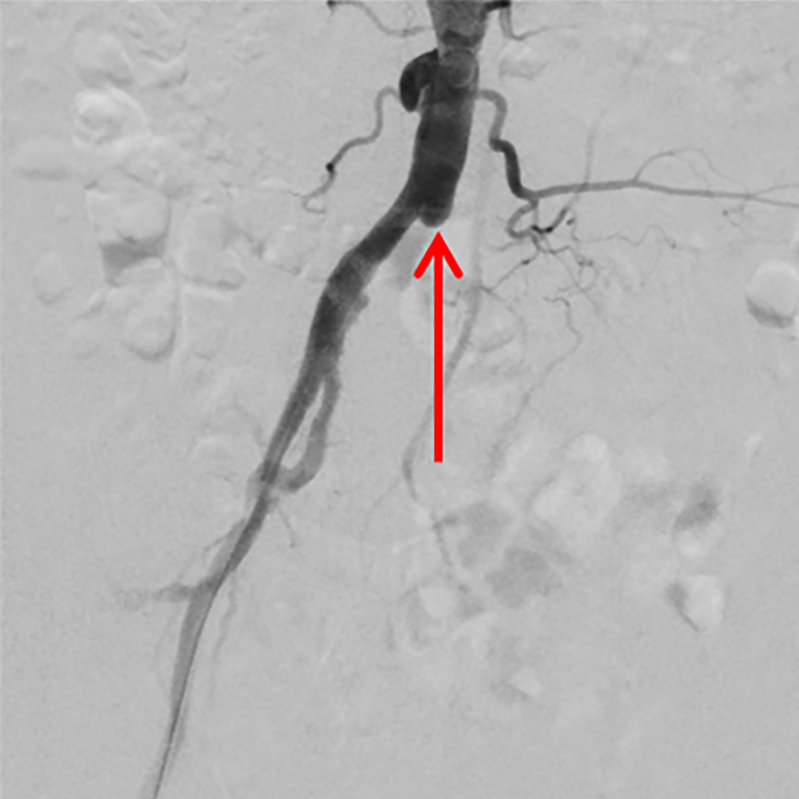

Bild 1b: Nach der Wiedereröffnung und dem Einsetzen einer Gefäßstütze (Doppelpfeil) kontrastiert sich das Gefäß wieder in ganzer Länge.